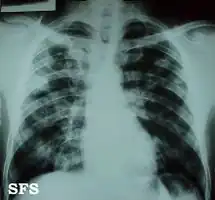

Chest X-ray